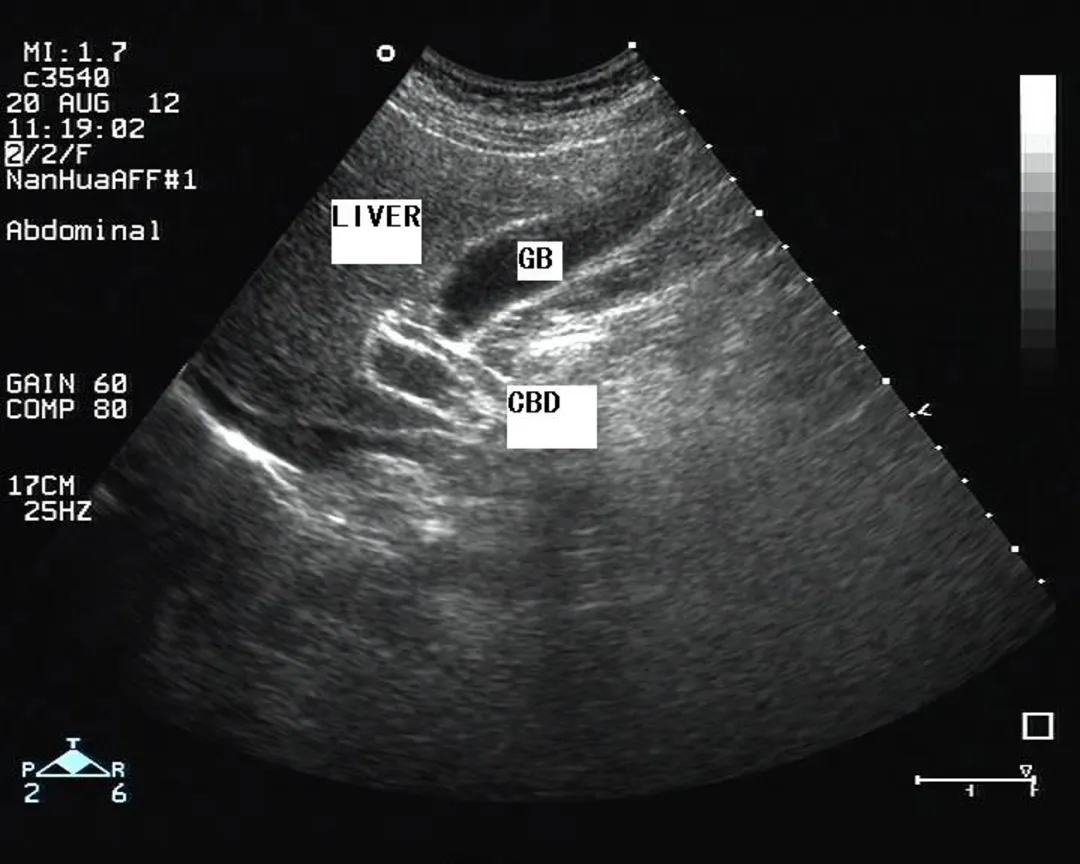

正常超声表现

胆囊位于胆囊窝内

纵切面呈梨形

横切面呈圆形或椭圆形

长径50~80mm, 横径30~40mm,胆囊壁厚度不超过3mm,多数小于2mm。

1:胆囊颈;2:胆囊体;3:胆囊底;4:胆囊皱褶

探头置于右肋缘下,大致与肋弓垂直,左右侧动探头,显示较完整的胆囊长轴断面,测量胆囊的长径和横径。

正常值:长径<10cm,横径<3.5cm